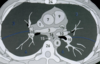

TC ventana pulmonar

Se ven mejor la vía aérea, vasos pulmonares y cisuras, pero todas las estructuras mediastínicas aparecen de un tono gris demasiado similar.